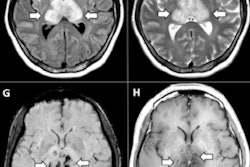

The researchers trained and tested two versions of a 3D convolutional neural network (CNN) to perform ordinal, or multiclass, classification using 508 3D SPECT images from the nuclear medicine department of the Hospital Reina Sofía in Córdoba, Spain. All patients in the study had received the ioflupane iodine-123 radiopharmaceutical prior to SPECT imaging and had been classified into one of four categories of disease severity based on the radiologist's assessment of the dopaminergic activity in the nigrostriatal dopaminergic pathway.

Of the 508 images, 314 (61.8%) were of healthy patients (class 0), while 41 (8.3%) had a slight alteration (class 1) to the nigrostriatal dopaminergic pathway. More advanced alteration (class 2) was seen in 52 (10.2%) patients and severe alteration (class 3) was evident in 100 (19.7%) of the images.